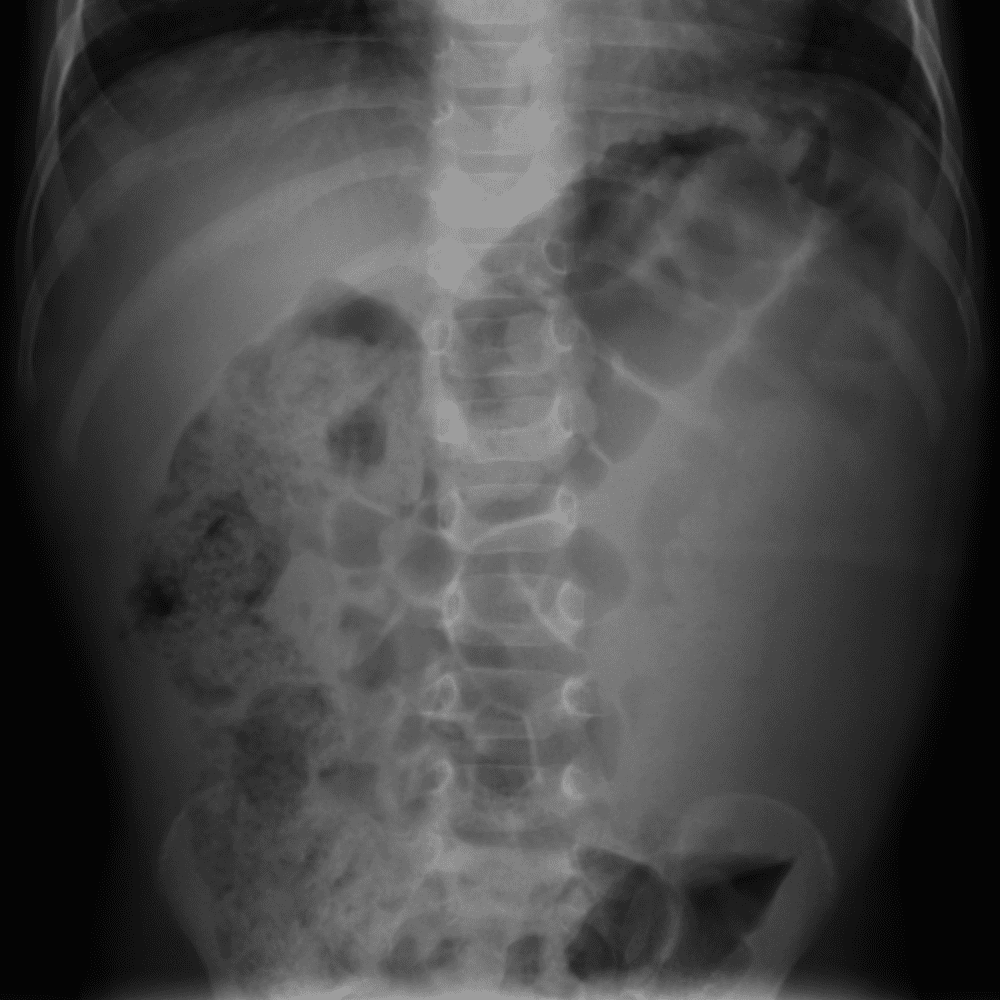

Practice Cases